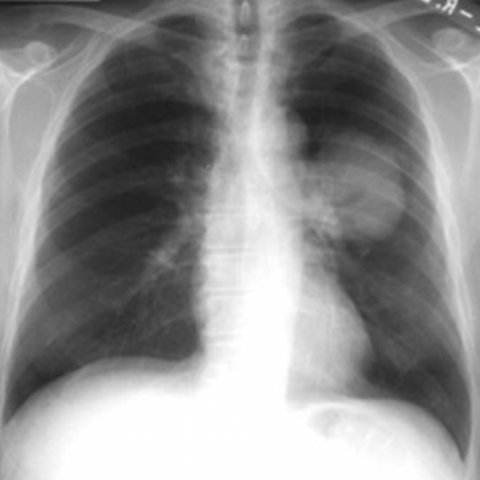

Gunnar Mýrdal Einarsson, sérfræðingur í brjóstholsskurðlækningum og yfirlæknir, er látinn.